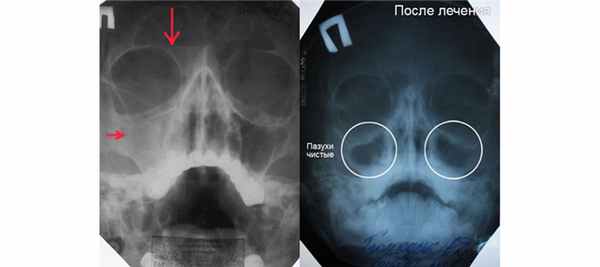

Ниже вы видите снимок гайморита до и после лечения. Рентгенограмма расшифровывается лечащим врачом, либо рентгенологом.

На изображении наглядно показано, как выглядит гайморит на снимке до и после лечения. На признаки воспалительного процесса указывают следующие изменения:

Патологические изменения могут наблюдаться как с одной стороны, так и с обеих сторон.

После проведенного лечения, когда воспалительный процесс полностью устранен, наблюдается следующая картина:

- Отчетливо видны границы носа и перегородки.

- Носовые пазухи светлые, границы четкие.

- Лобные пазухи локализованы над глазницами, тёмных пятен не наблюдается.

Обратите внимание, что интерпретацию результатов проводит только лечащий врач. Не пытайтесь заниматься самодиагностикой.